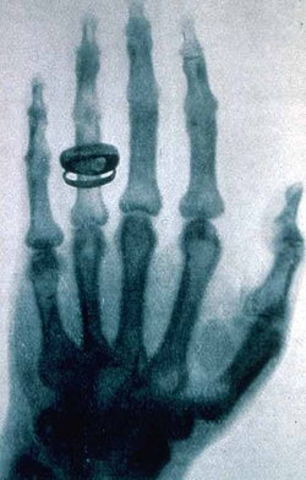

La denominación rayos x designa a una radiación electromagnética, invisible para el ojo humano, capaz de atravesar cuerpos opacos y de imprimir las películas fotográficas.. Los actuales sistemas digitales permiten la obtención y visualización de la imagen radiográfica directamente en una computadora (ordenador) sin necesidad de imprimirla.